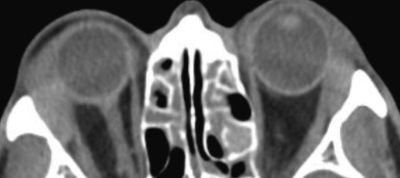

血液所見:赤血球 423 万、Hb 12.9 g/dL、Ht 37 %、白血球 6,400、血小板 21 万。血液生化学所見:尿素窒素 13 mg/dL、クレアチニン 0.5 mg/dL、総蛋白 8.5 g/dL、アルブミン 3.9 g/dL、IgG 3,305 mg/dL (基準 960〜1,960)、IgA 159 mg/dL (基準 110〜410)、IgM 67 mg/dL (基準 65〜350)、IgE 350 IU/mL (基準 250 以下)、総ビリルビン 0.9 mg/dL、AST 22 U/L、ALT 16 U/L、γ-GTP 34 U/L (基準 8〜50)、アミラーゼ 122 U/L (基準 37〜160)。免疫血清学所見:抗核抗体陰性、リウマトイド因子<RF>陰性。眼窩部単純CT及び腹部造影CTを別に示す。